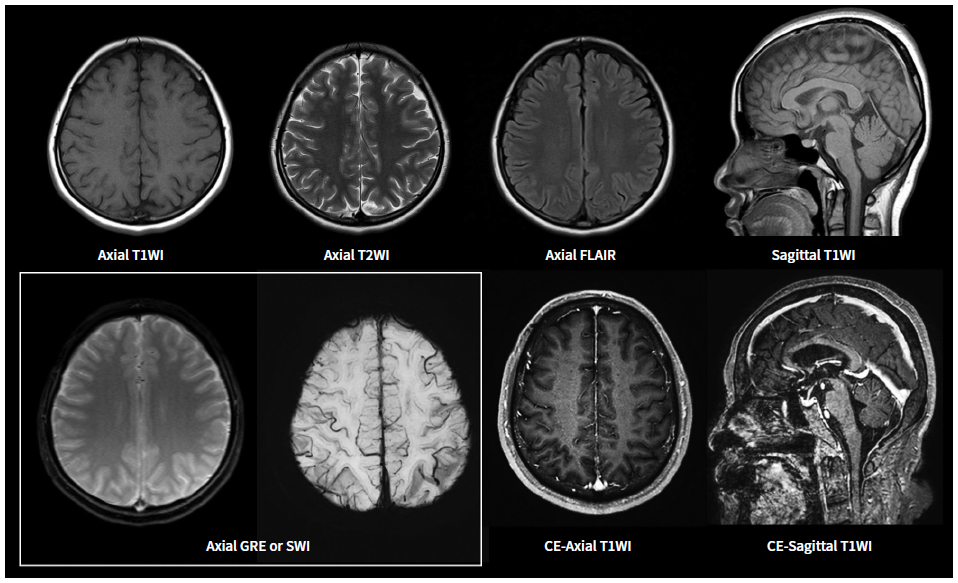

MRI(자기 공명 영상)은 강력한 자기장과 라디오파를 이용하여 체내 조직의 이미지를 생성하는 기술입니다. MRI는 연부 조직, 즉 뇌, spinal cord, 근육, 그리고 다양한 내장 장기 등을 상세하게 볼 수 있는 특징이 있습니다. 주로 신경계, 근골격계 및 종양 연구의 진단 도구로 사용됩니다.

MRI는 인체 내의 수소 원자의 자기적 성질을 이용하여 이미지를 생성합니다. 강력한 자기장이 수소 원자를 정렬시킨 후, 라디오 파를 통해 이들을 자극하여 방출되는 신호를 수집합니다. 수집된 신호는 컴퓨터에 의해 해석되어 이미지를 만들어 내는데, 이 과정에서 세부적인 이미지가 생성되어 체내 구조를 명확하게 볼 수 있게 됩니다.